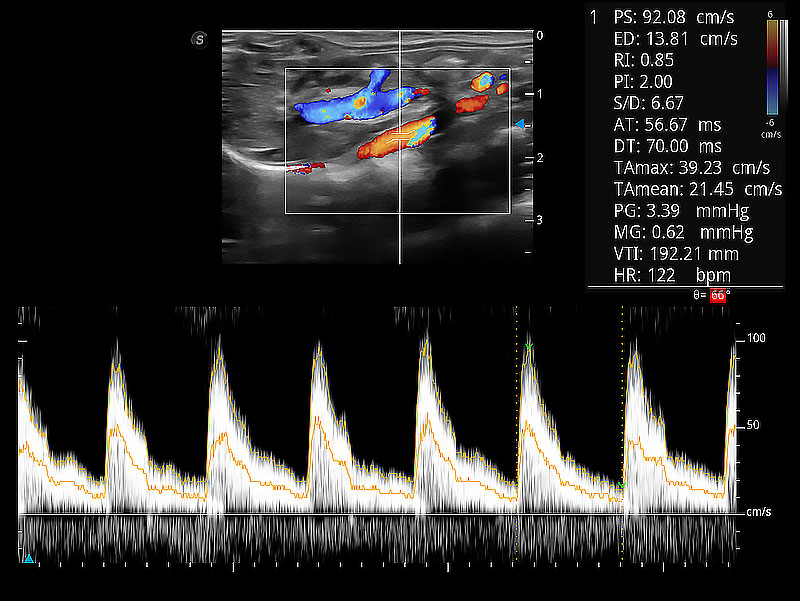

極大提升超低速微細(xì)血流的檢出能力,同時(shí)更精準(zhǔn)地濾除軟組織和超聲信號(hào),為獸用醫(yī)生提供以往無(wú)法通過(guò)常規(guī)血流獲得的疾病診斷信息。

在傳統(tǒng)二維血流成像的基礎(chǔ)上,呈現(xiàn)血流的立體感,具有動(dòng)感的生命力之美。即便是微小的血管也能輕松應(yīng)對(duì),提高了血流的視覺(jué)敏感性。

隨著取樣門(mén)位置改變,頻譜多普勒包絡(luò)可進(jìn)行自動(dòng)眼蹤測(cè)量,且可自由配置測(cè)量的參數(shù)。